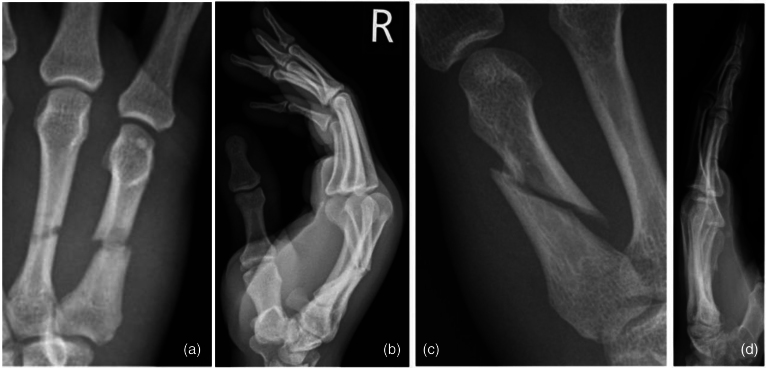

Abstract Image